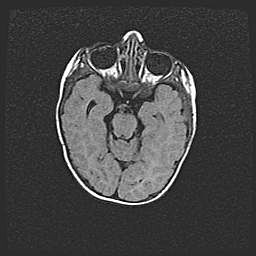

Аномалия Денди-Уокера. Признаки гипоплазии мозолистого тела.

Возраст: 5 месяцев 3 дня

Вес: 5550 г

Пол: мужской

Окружность головы: 39 см

Срок гестации: 40 недель

Аномалия Денди-Уокера – это порок развития головного мозга, для которого характерна триада симптомов: гипотрофия или аплазия червя мозжечка и/или полушарий мозжечка, расширение четвёртого желудочка с формированием ликворной кисты задней черепной ямки, гипертензионная гидроцефалия различной степени.

Гипоплазия мозолистого тела относится к дефектам внутриутробного этапа развития мозговой ткани, возникающим в процессе закладки структур головного мозга, что происходит на начальных этапах развития эмбриона.